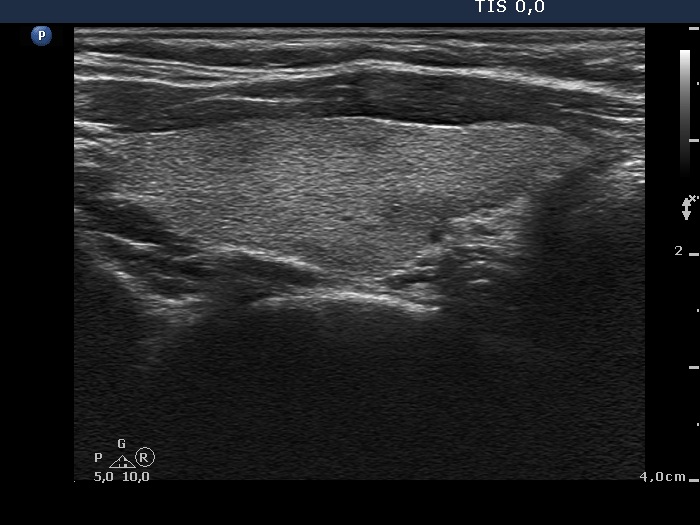

Follow-up 6 months after the first visit (3rd row of images):

Clinical presentation: The patient had no complaints.

Palpation: no abnormality.

Laboratory tests: TSH 2.06 mIU/L, FT4 13.3 pM/L, CRP 0.3 mg/L.

Ultrasonography: The pattern of the entire thyroid became almost completely normal. Only small hypoechoic areas were observed.

Suggestion: TSH in six months, in the event of pregnancy at once.

Follow-up 5 years later (3rd row of images):

Clinical presentation: Six months after the previous visit the patient became pregnant. The TSH was 5.91 mIU/L at the 5th gestational weeks. Replacement therapy was given which was ceased after delivery. The patient was free of complaints and the TSH was in the normal range, even during a next pregnancy 2 years later. Recently, a few weeks after COVID-19 infection, she noticed tenderness in the right side of the neck.

Laboratory tests: TSH 1.72 mIU/L, CRP 3.5 mg/L.

Ultrasonography: The thyroid was intact.